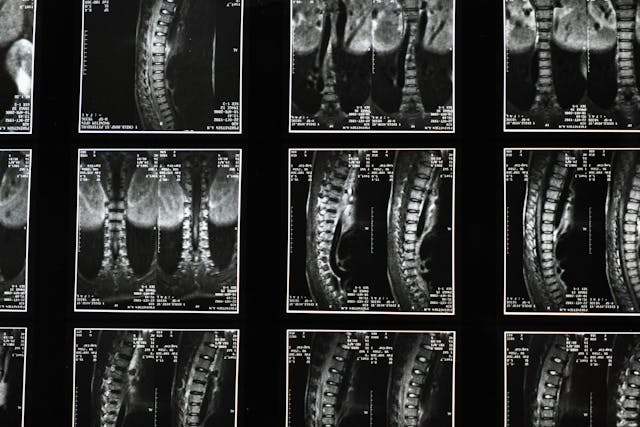

Bolesti páteře nás mohou trápit v každém věku. První problémy mohou mít už děti školou povinné a o bolestech ve vyšším věku vám poví snad každý. Páteř je skutečně osou našeho těla a pokud se k ní nechováme hezky, brzy nám o sobě dá vědět. Každodenní sezení v práci, doma u televize, nedostatek pohybu, to vše postupně naši páteř zatěžuje a divili byste se, co všechno s páteří může souviset. Běžným projevem problémů s páteří je bolest hlavy. Převážně může jít o krční páteř, ale není to podmínkou. Ale víte, že od páteře mohou být také žaludeční problémy nebo bolí vás zápěstí? Možná myslíte, že je to problém s karpály, ale i tady může jít o zablokovanou krční páteř a přetěžování ramene.